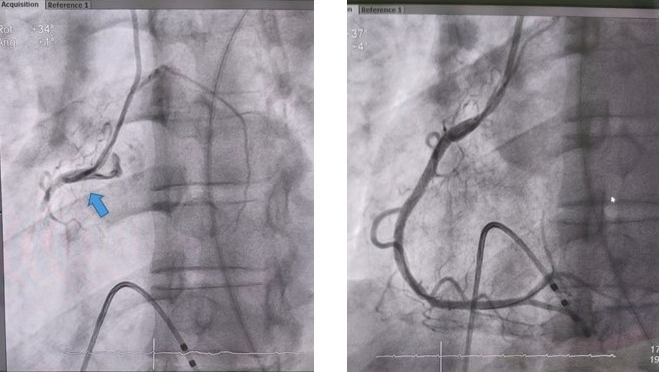

Tại Khoa Tim mạch can thiệp, bệnh nhân được đặt máy tạo nhịp tạm thời với điện cực trong buồng thất phải, chụp động mạch vành qua da. Kết quả cho thấy bệnh nhân bị tắc hoàn toàn đoạn gần động mạch vành phải.

Hình ảnh tắc động mạch vành phải cấp tính gây nhồi máu cơ tim (hình trái) và động mạch vành được tái thông bằng stent. Ảnh: BVCC

Người bệnh được xử trí hút huyết khối và đặt stent vào đoạn gần động mạch vành phải. Sau can thiệp, bệnh nhân hồi phục nhanh, cải thiện hoàn toàn triệu chứng đau ngực và đẩy lùi nguy cơ tắc nghẽn mạch vành gây nhồi máu cơ tim cấp.